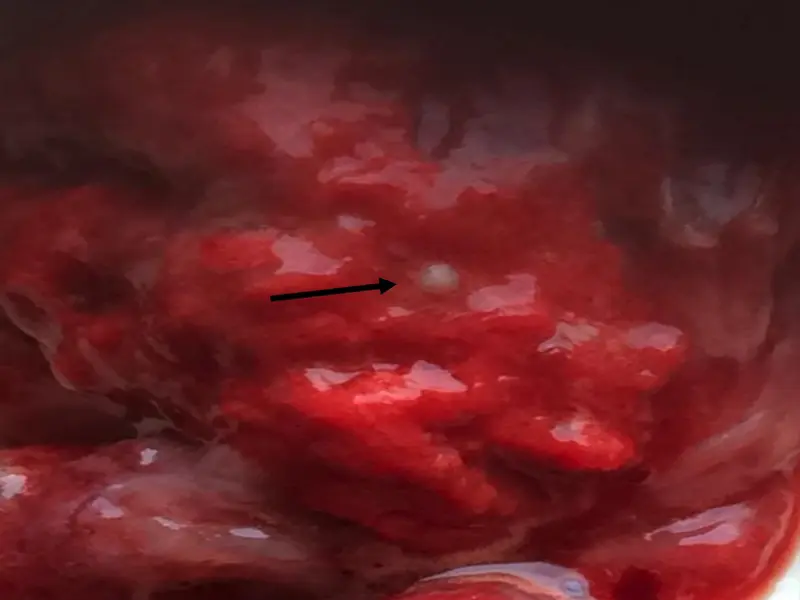

Anatomopathological examination revealed numerous fungal nodules in the lungs (Fig. 1 and 2).

Fig.1 Fungal nodules in the lungs